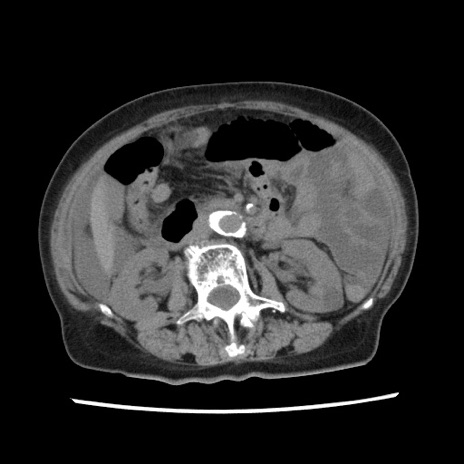

冠状断像

【症例】80歳代女性

【主訴】腹痛

【現病歴】8時間前から腹痛あり来院。

【既往歴】糖尿病、脂質異常症、子宮体癌にて子宮全摘術

【身体所見】意識清明・会話良好だが腹痛で苦悶様、全腹部にわたって反跳痛と圧痛あり

【データ】WBC 13600、CRP 0.14、LDH 224、CK 90